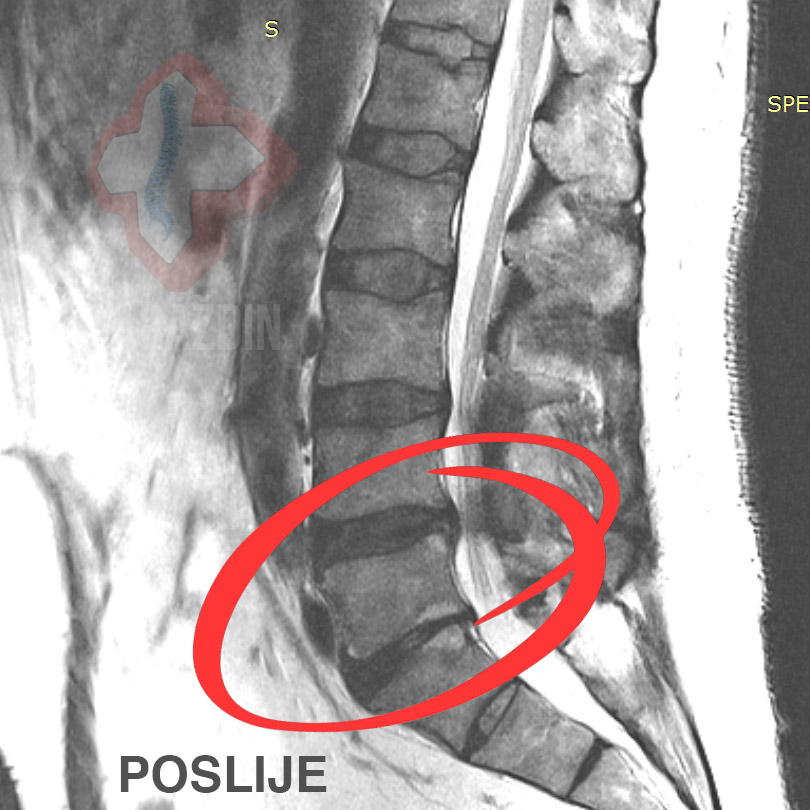

Primjer 1

Klijent se javlja u Nado centar sa snimkom na kojoj je

vidljiva sekvestacija diska. Kod klijenta je prisutna bol u

križima preko lijevog gluteusa duž lijeve noge uz lagane trnce u

potkoljenici. Nakon konzultacija i utvrđenog optimalnog tijeka

liječenja, klijentu se kroz 15 dekompresijskih

tretmana sekvestar razgradio.